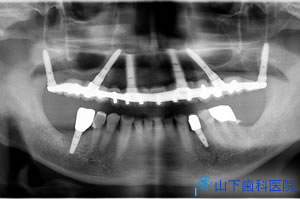

| 初診時のレントゲン写真です。 | ![]() |